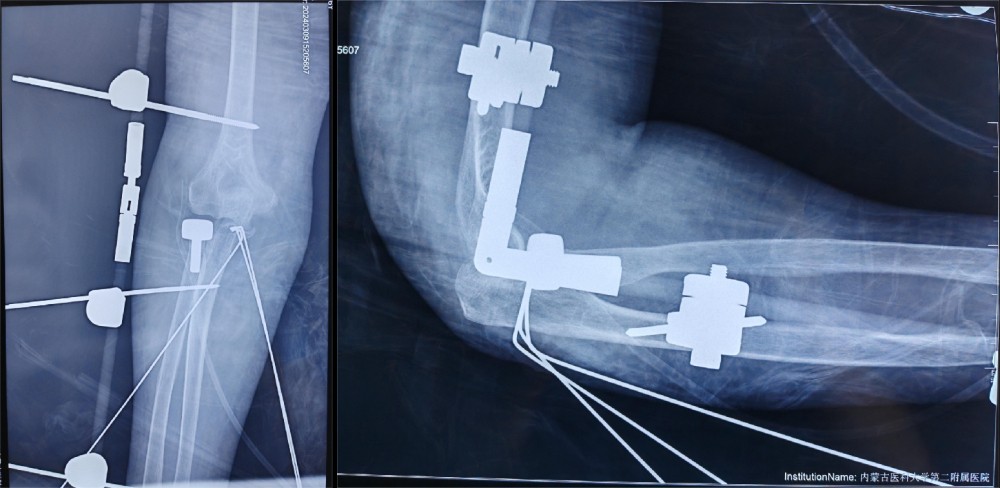

结合患者年龄及损伤类型,按照肘关节恐怖三联征的标准化治疗理念,副院长冯卫教授、创伤外科中心A区团队与李庭教授充分沟通、讨论后,由李庭教授及冯卫教授团队共同为患者施行标准化的治疗:“单一肘关节外侧切口,进行右冠状突骨折切开复位内固定术,右桡骨头粉碎性骨折桡骨头置换术,右肘关节外侧副韧带修复术,术中见右肘关节仍不稳定,随后给予右肘关节外固定架固定术”。标准化的治疗流程,使得这位高龄患者达到了与北京积水潭医院同质化的治疗。